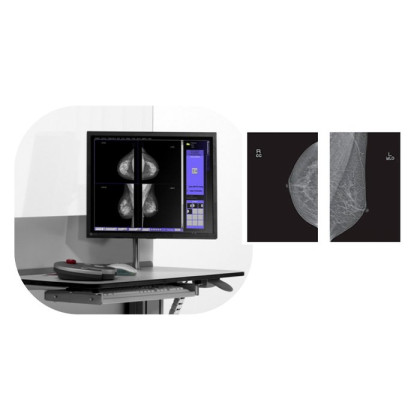

Маммограф PINKVIEW-AT DR Plus Expert — не просто медицинское оборудование, а передовое решение, сочетающее в себе инновационные технологии и высокие стандарты диагностики. Предназначенный специально для раннего диагностирования рака молочной железы, прибор стоит на страже здоровья женщин.

Устройство оборудовано плоскопанельным полноформатным детектором цифрового типа, который работает вместе с генератором и рентгеновской трубкой. Эти технологические компоненты позволяют получить высококачественные фотографии, снижают уровень облучения и гарантируют комфорт для обследуемого.

Устройство революционизирует качество маммографических снимков, существенно улучшая их четкость и снижая уровень шума. Это не только делает процесс интерпретации результатов более простым для врачей, но и способствует более точному выявлению возникновения рака молочной железы на ранних стадиях. Аппарат обеспечивает высочайшую чувствительность к деталям и изменениям в тканях молочной железы.